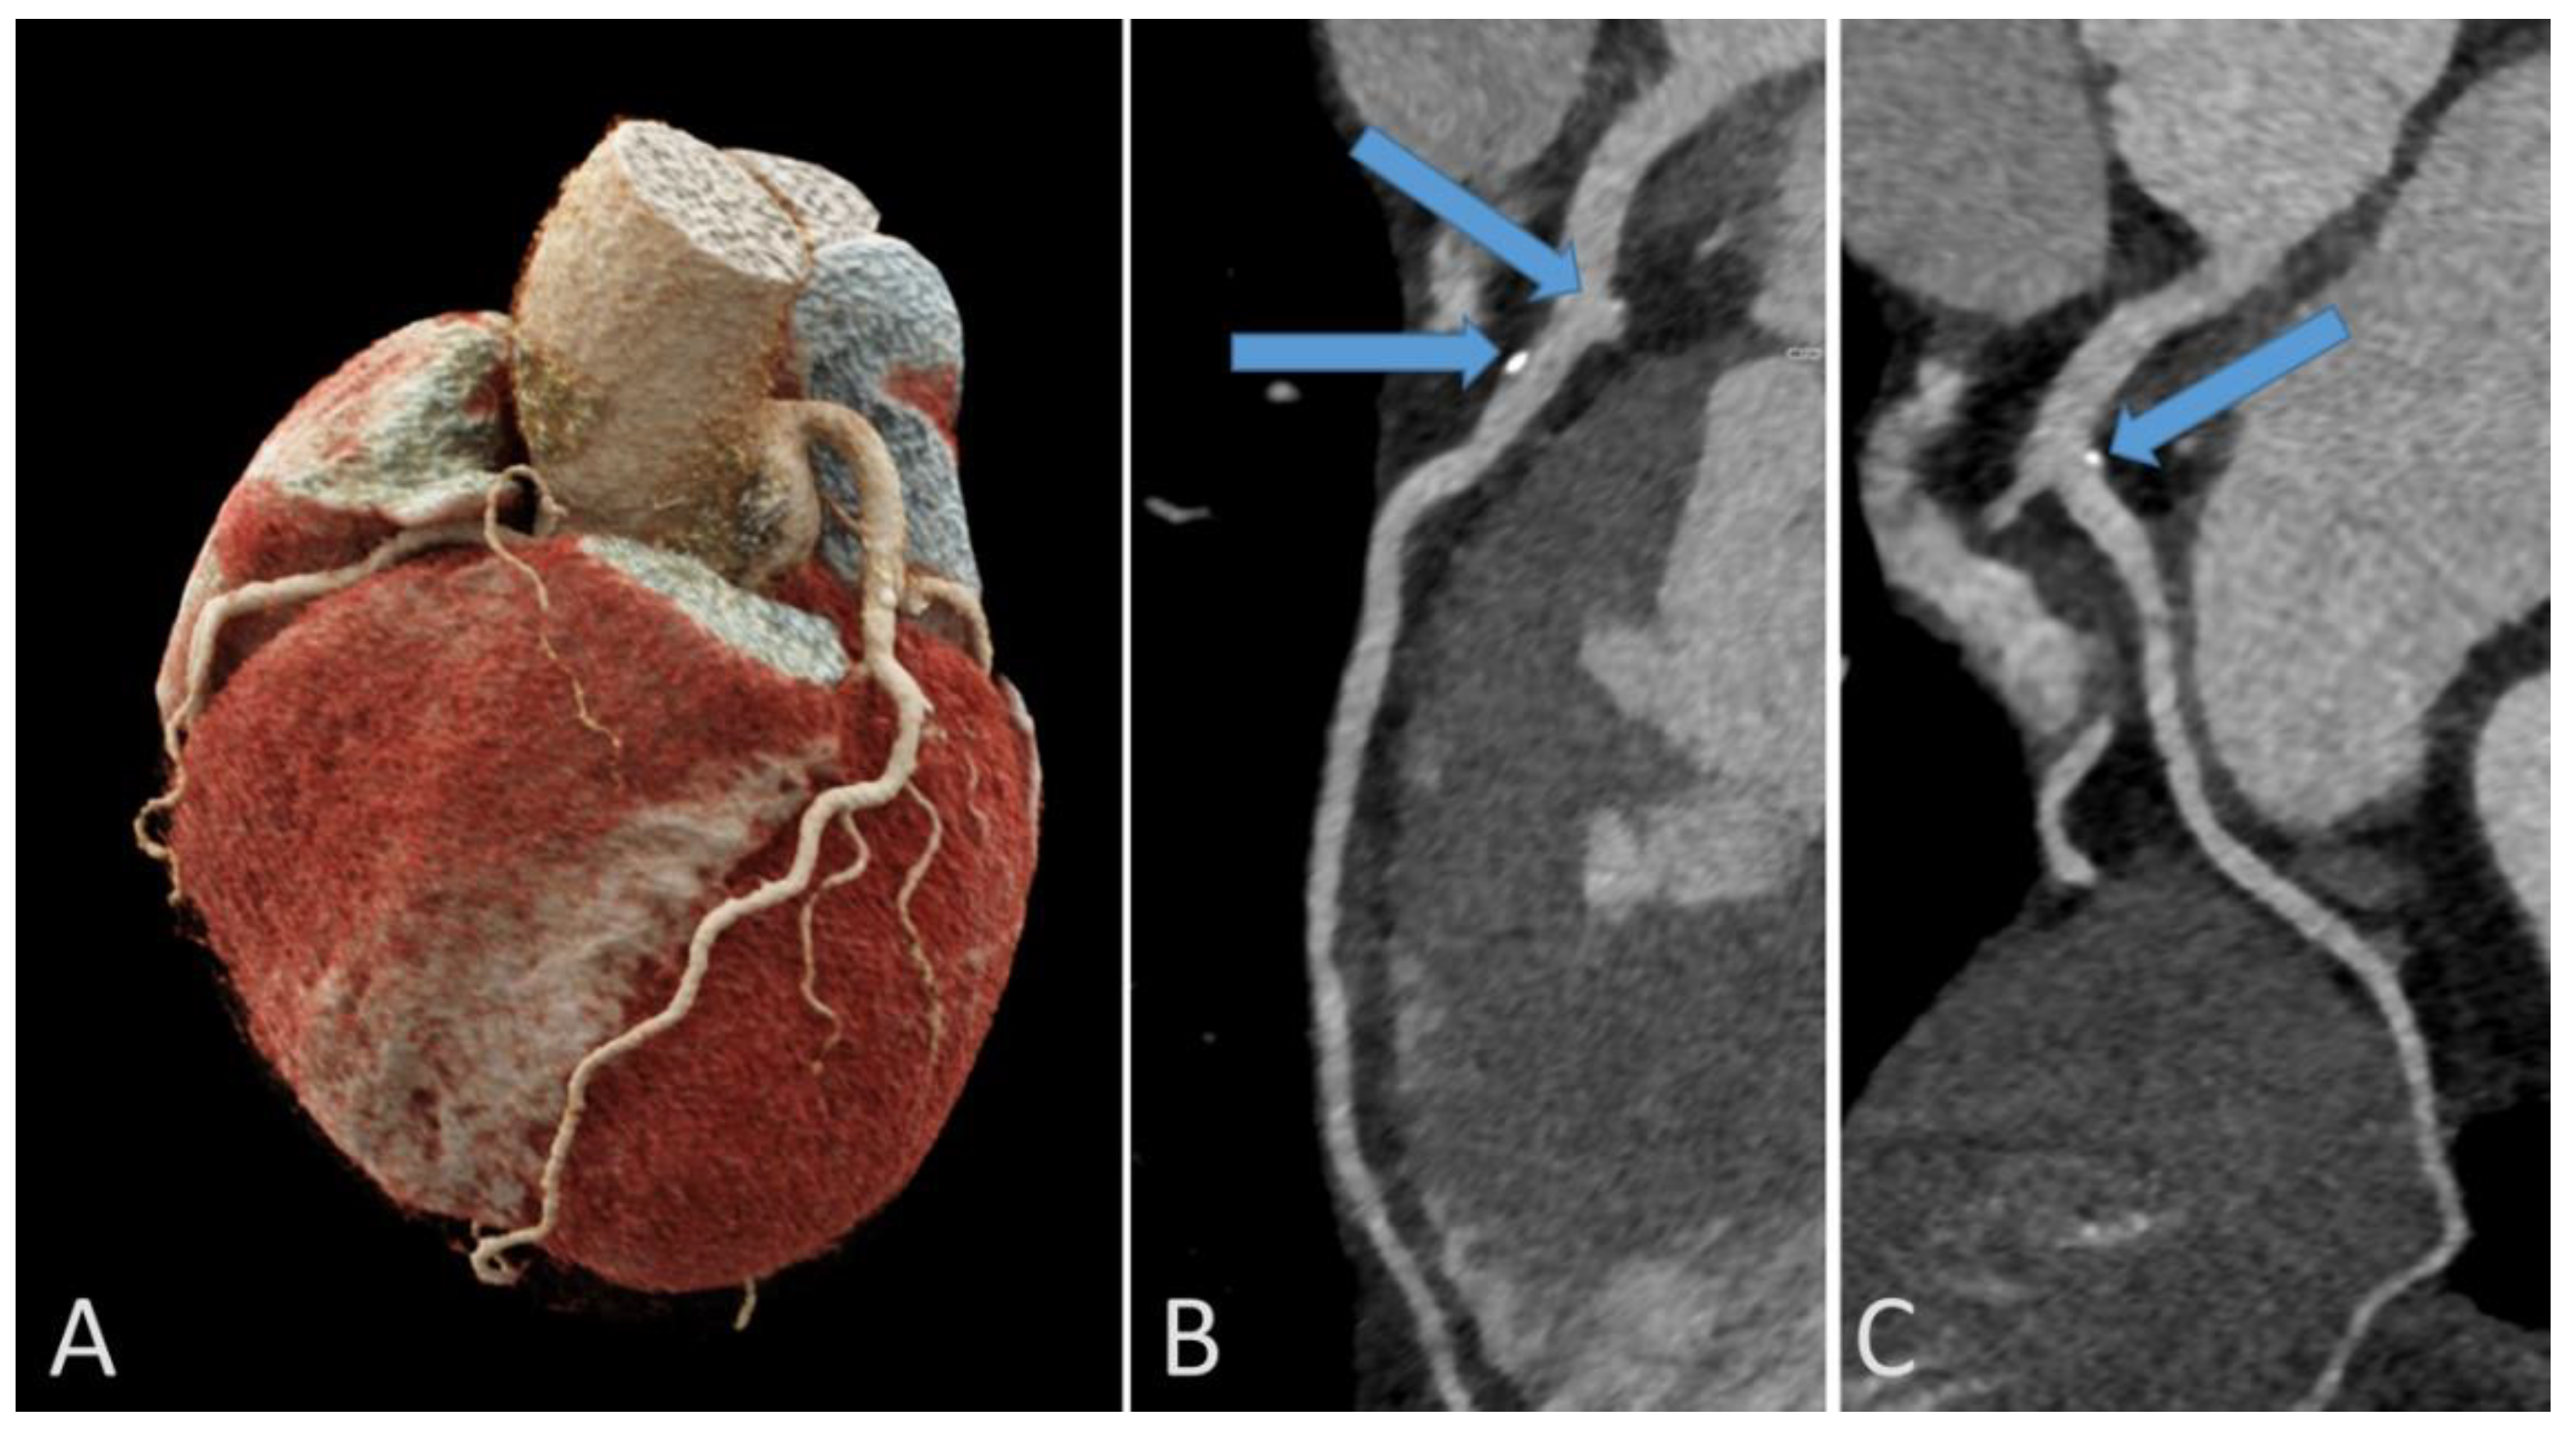

3.7. Coronary Artery Calcifications